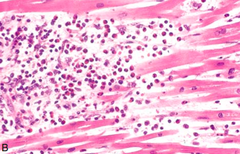

hemorrhage

Front

risks ulcers can cause

Back